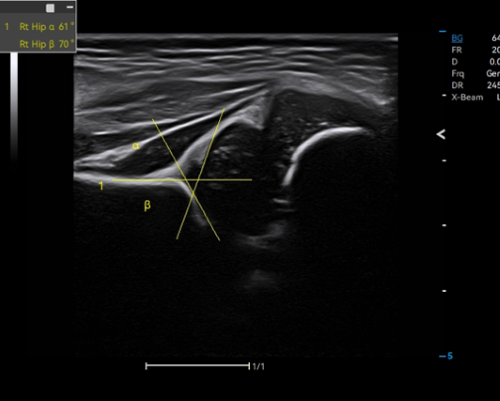

Pediatrics

Auto Hip identifies the baseline, tracks the top line of bone and cartilage, and measures crucial results for hip dysplasia evaluation.